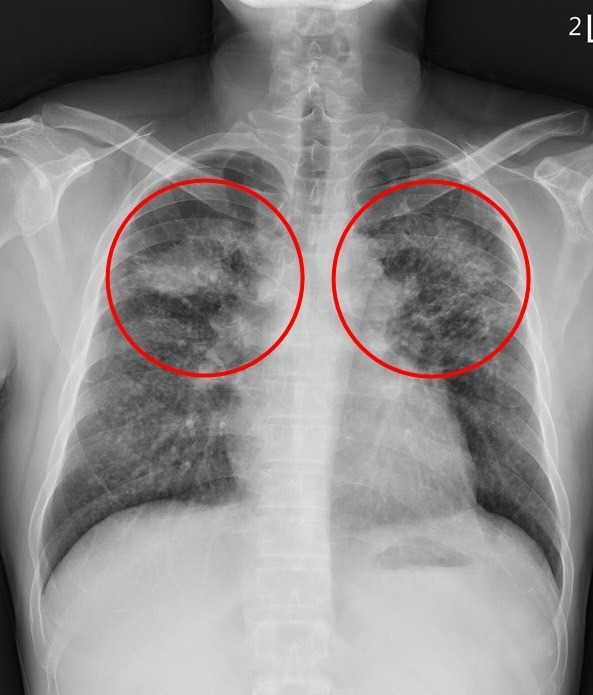

▲ 劉迪塑醫師指出,矽肺症患者的肺部因發炎反應和局部纖維化而產生許多間質性結節,嚴重時甚至會發展為漸進性大量纖維化,在雙上肺葉形成對稱的腫塊。(圖/花蓮慈濟醫院提供)